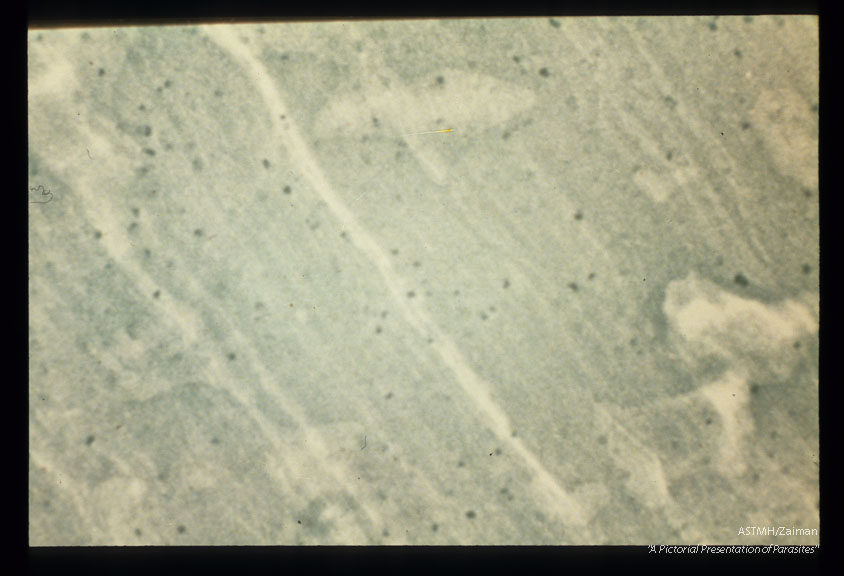

Xeroradiograph of bear muscle showing calcified cysts as small dense spots.

Trichinella spiralis

Description: Xeroradiograph of bear muscle showing calcified cysts as small dense spots.